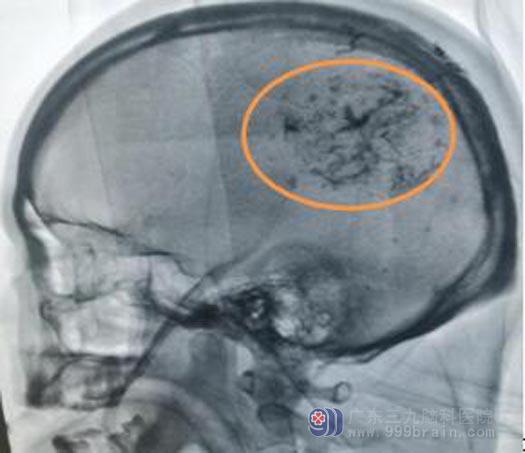

▲栓塞后显影

2020年1月8日在介入室行供血血管栓塞术后,当天鲁明团队又为叶先生实施了开颅肿瘤切除术。术中有惊无险,手术顺利完成,